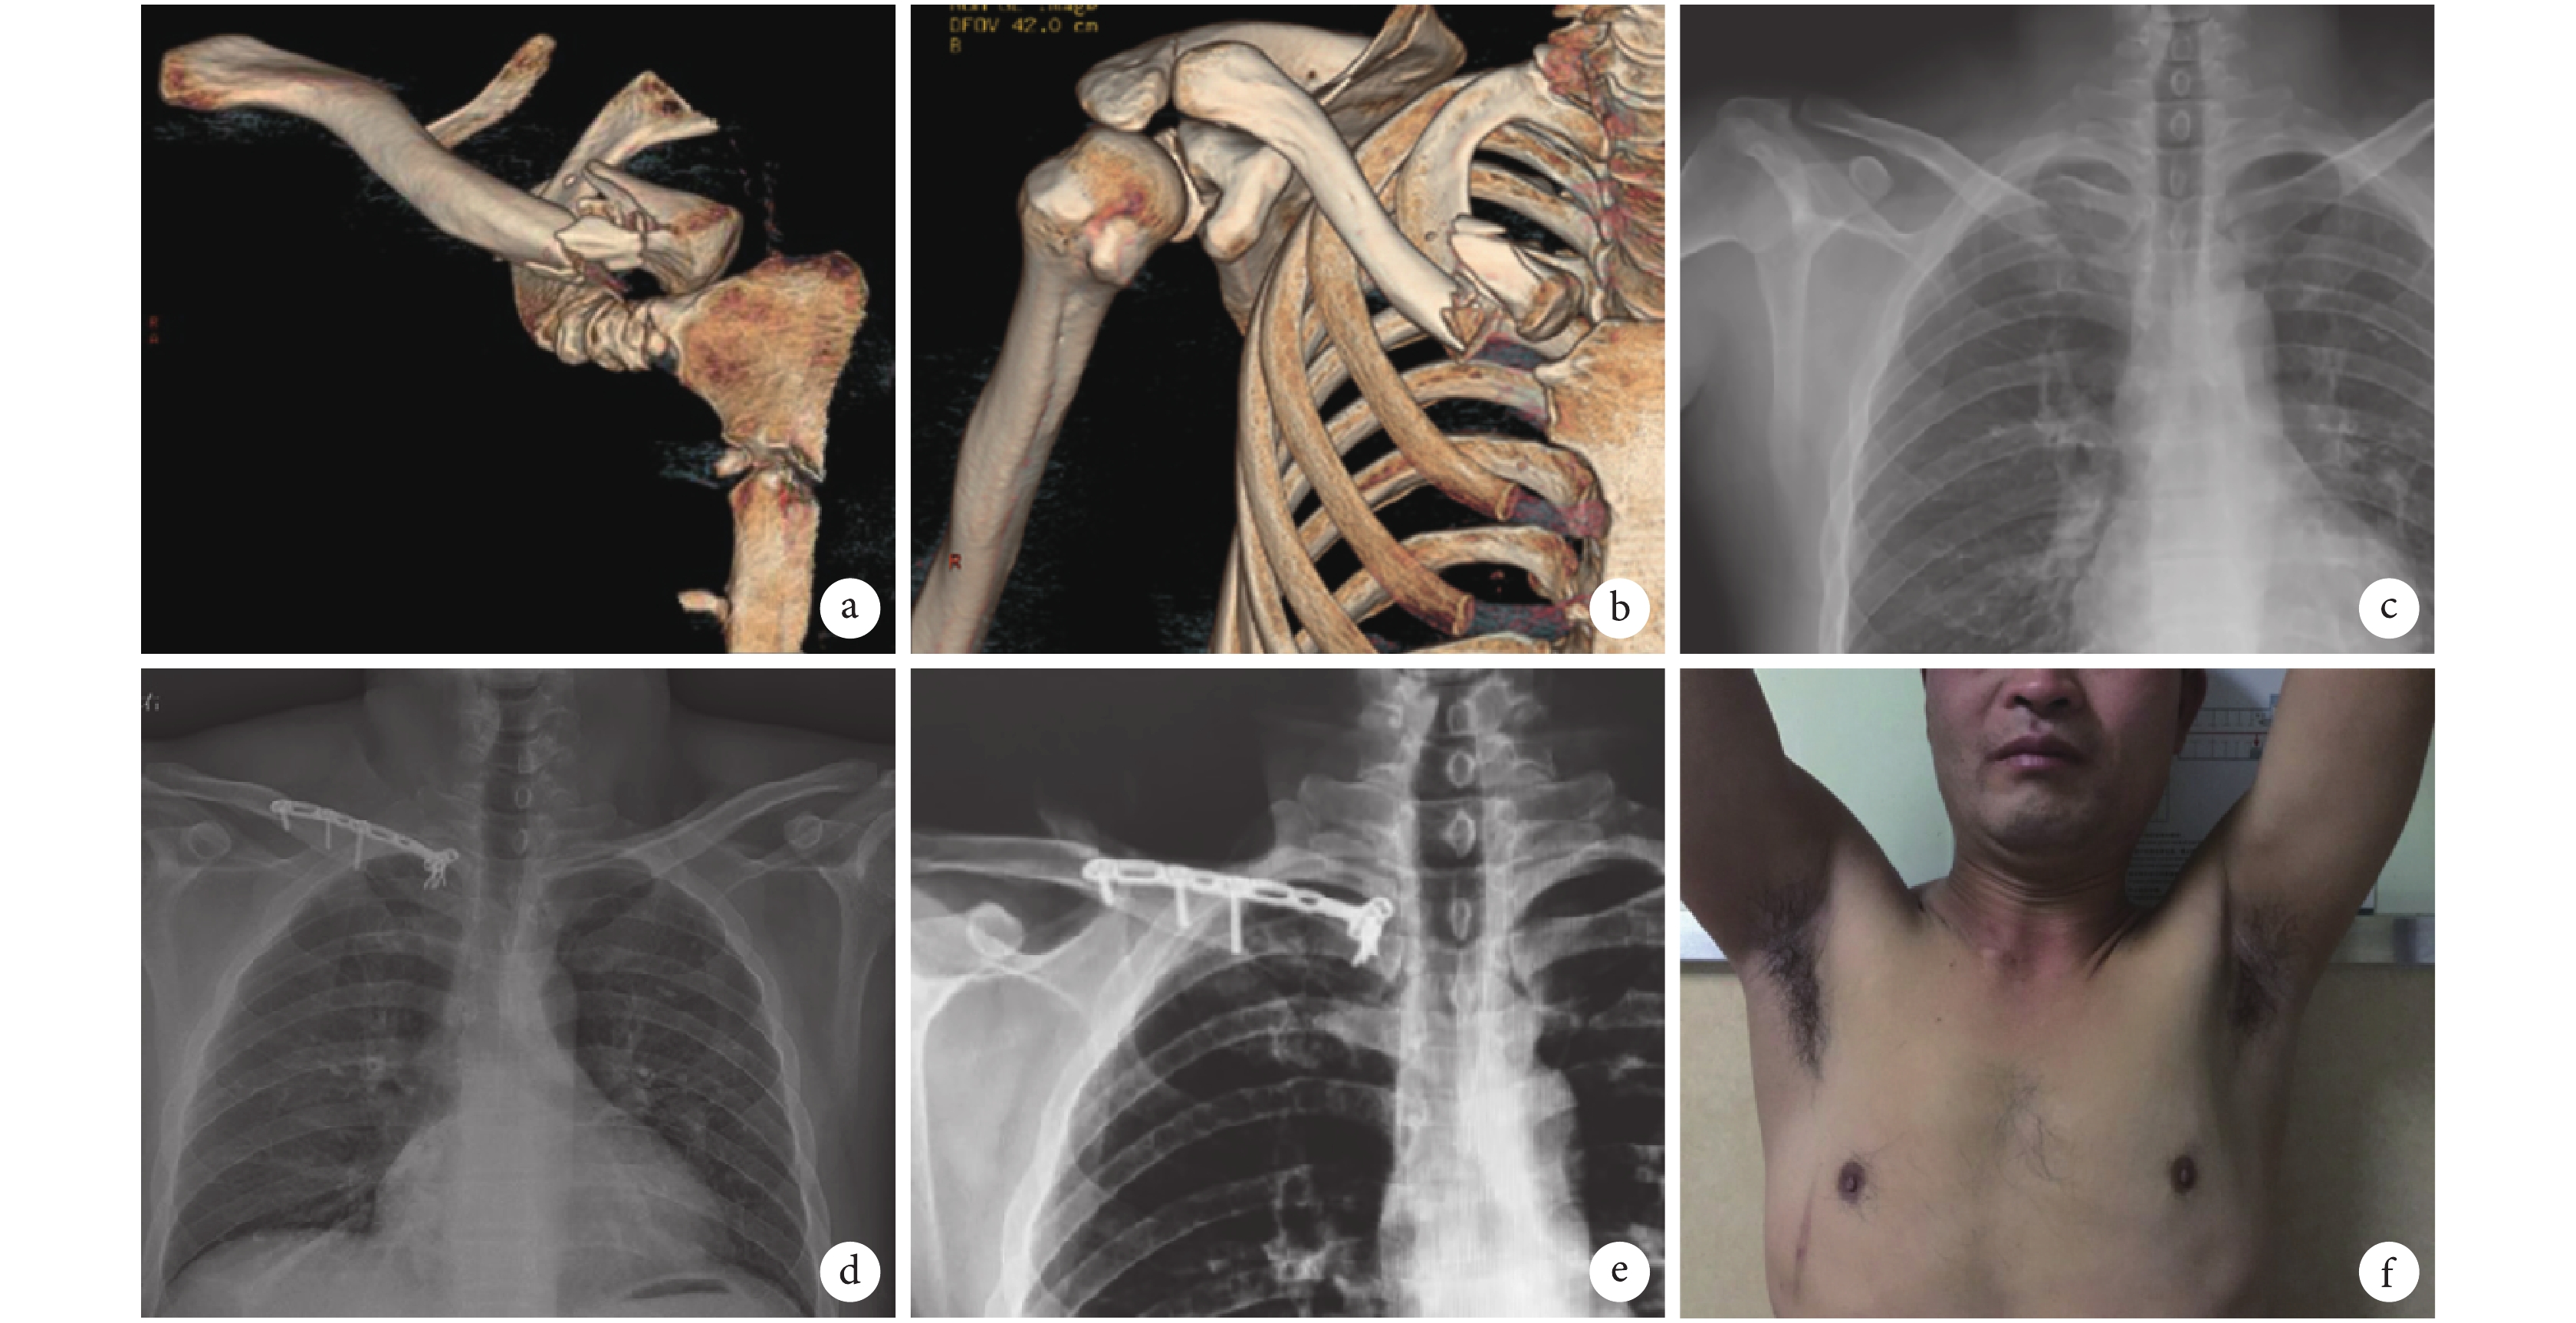

a、b. 術前 CT 三維重建;c. 術前 X 線片;d. 術后 1 d X 線片;e. 術后 6 個月 X 線片;f. 術后 1 年功能像

Figure2. A 48-year-old male patient with anterior dislocation of the left sternoclavicular joint caused by falling from hight in group Aa, b. Preoperative CT three-dimensional reconstruction; c. Preoperative X-ray film; d. Postoperative X-ray film at 1 day; e. Postoperative X-ray film at 6 months; f. Postoperative functional image at 1 year

兩組手術均順利完成。A 組手術時間、術中失血量及住院時間均顯著少于 B 組,差異有統計學意義(P<0.05);但兩組切口長度比較差異無統計學意義(P>0.05)。見表 2。兩組患者均獲隨訪,隨訪時間 18~30 個月,平均 24 個月。術后 3~6 個月兩組患者骨折均愈合,胸鎖關節無再次脫位。A 組發生胸鎖關節疼痛 1 例,切口感染 2 例;B 組發生胸鎖關節疼痛 1 例,內固定松動 1 例,胸鎖關節再次脫位 1 例;兩組并發癥發生情況比較,差異無統計學意義(P=1.000)。兩組患者術后各時間點 Rockwood 評分均較術前明顯改善。術后 1 個月,A 組 Rockwood 評分顯著高于 B 組,差異有統計學意義(t=2.270,P=0.031);術后 6 個月及末次隨訪時兩組 Rockwood 評分比較差異無統計學意義(P>0.05)。見表 1。末次隨訪時根據 Rockwood 評分標準,A 組獲優 13 例,良 2 例,可 1 例,優良率 93.75%;B 組獲優 11 例,良 4 例,可 1 例,優良率 93.75%;兩組比較差異無統計學意義(Z=–0.748,P=0.455)。見圖 2、3。